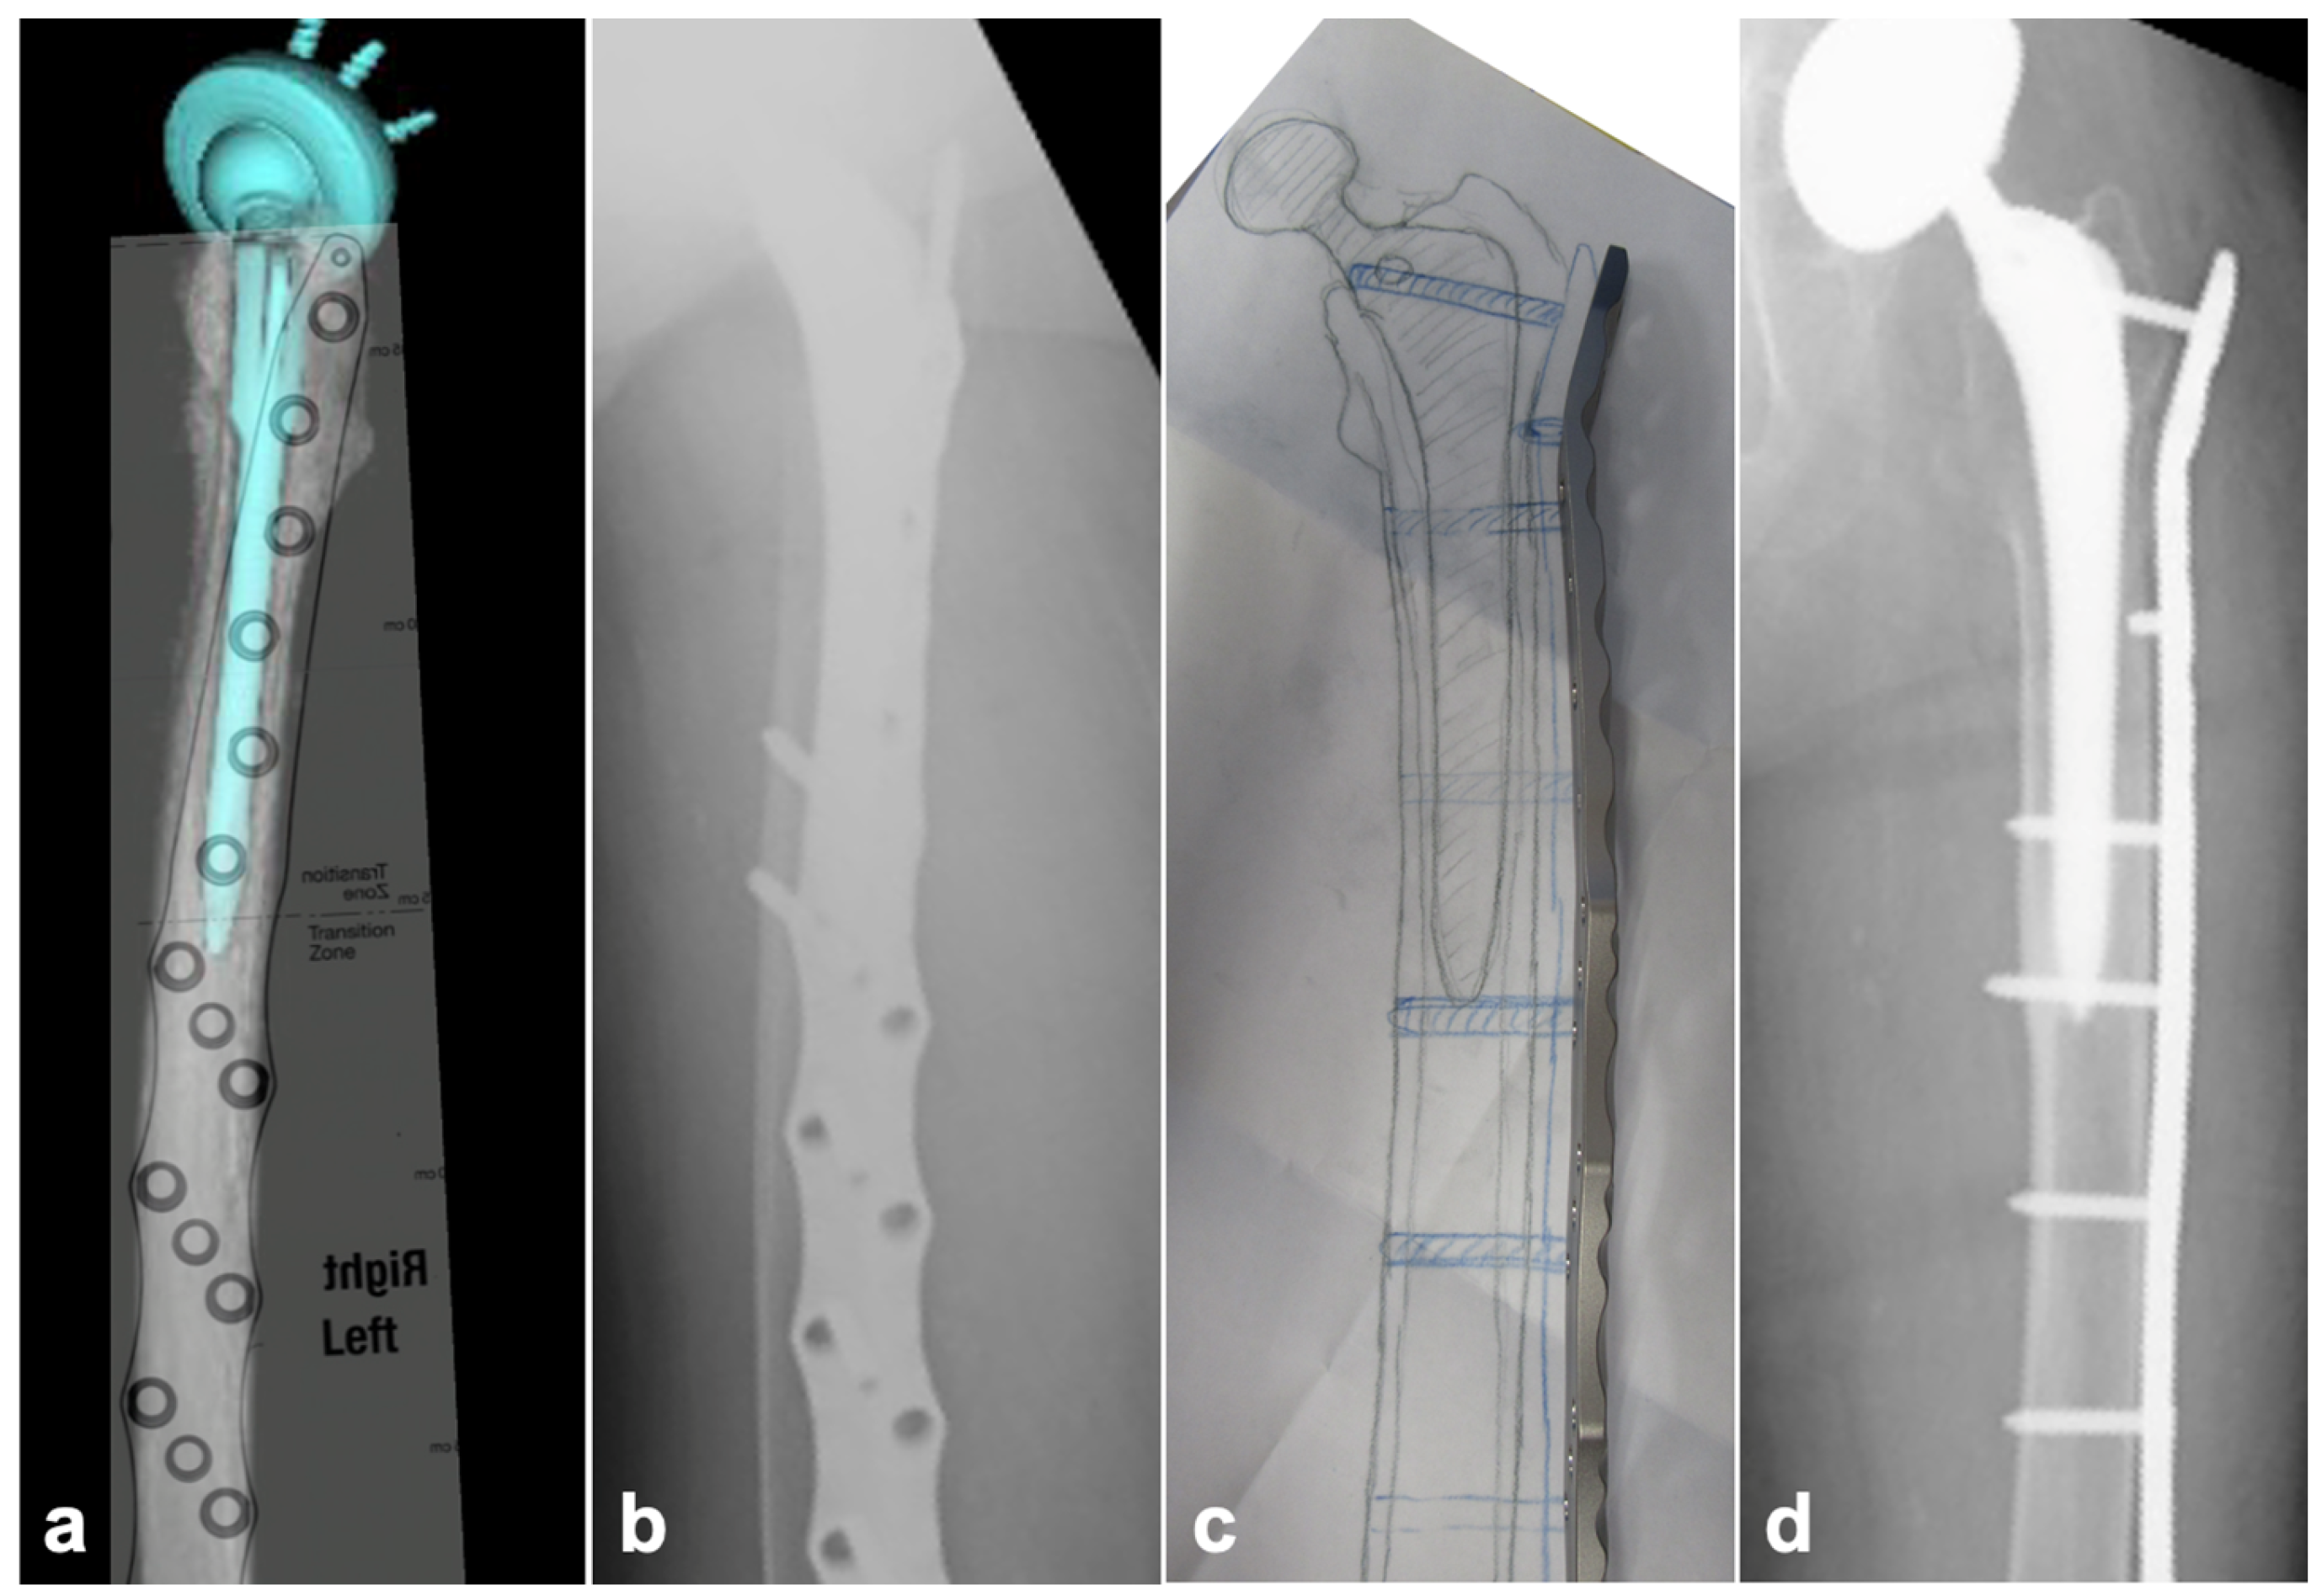

2.2. Preoperative Planning

2.3. Surgical Technique

2.3.2. SFN